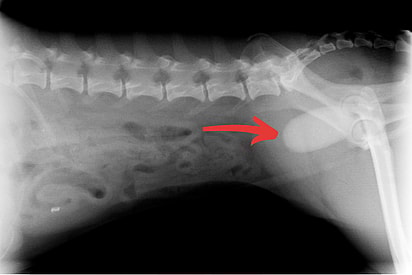

Bladder Stones

Any bladder instruction can cause incontinence. In the case of a dog peeing in sleep, this is most likely to be bladder stones. This damages the muscles of the bladder, which results in urine leakage. Other than stones, bladder tumors and polyps can also cause incontinence. Bladder cancer is rare in dogs, but it can also lead to nighttime accidents. This usually isn’t the first symptom, but if your dog is known to have bladder cancer, you might want to consider diapers or potty pads.